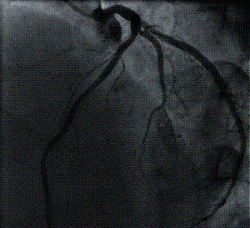

Coronary Angiography is a procedure to visualise the coronary arteries. The coronary arteries are the blood vessels that supply blood to the heart muscles. On ordinary chest X-ray films, the heart appears as a silhouette and the coronary arteries cannot be seen. To see the coronary arteries, a special dye or contrast medium is injected through a small tube (catheter) inserted into a large artery in the groin or the wrist. The catheter is then advanced to the heart and positioned at the mouths of the coronary arteries before injection is performed.

Coronary angiography is therefore an invasive procedure. Sometimes, another procedure called a left ventriculography is performed at the same session, whereby a catheter is advanced into the left ventricle (the lower and larger heart chamber) and contrast medium is injected. This allows visualisation of the left ventricle and its contractions.

Coronary Angiography is carried out to determine whether there is any significant narrowing or blockage in the coronary arteries. Once determined, the doctor will decide on the best form of treatment to carry out.

It is also performed before Coronary Angioplasty (ballooning) is carried out to provide a 'road map' for guiding the Angioplasty procedure.